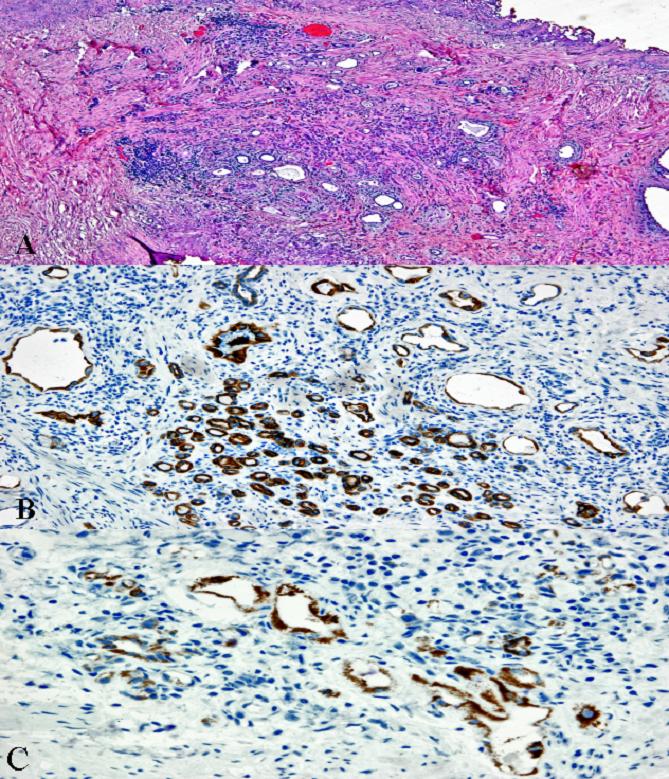

Adenoma nefrogénico prostático. A propósito de un caso

El adenoma nefrogénico es una lesión pseudotumoral rara de origen urotelial que afecta preferentemente a la vejiga urinaria, y que ha recibido varios nombres en la literatura. Se caracteriza por ser una entidad benigna asociada a ciertos estados irritativos de la vía urinaria. Debido a ello, se ha sugerido que su naturaleza puede corresponder a una metaplasia del urotelio. Existen pocos casos documentados de adenoma nefrogénico de localización prostática (metaplasia nefrogénica). Describimos nuestra experiencia y revisamos la bibliografía. Nuestro objetivo es poner en relevancia la rareza de esta patología y sus implicaciones terapéuticas.Descargas